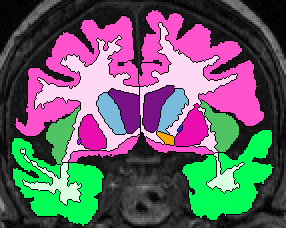

| Temporal Lobe White Matter: Anteriorly, simply relabel the cerebral white matter in the temporal lobe as temporal lobe white matter (fig 2). When the white matter becomes continuous from the temporal lobe to the frontal, draw a horizontal line laterally from the inferior Insula, then extract the temporal white matter, leaving it unlabeled for the time being (fig 3- this image show it labeled, however). Once the frontal lobe gray matter superior to the amygdala is gone, draw a straight horizontal line from one fronto-temporal junction (lateral sulcus) to the other and extract the temporal white matter (fig 4).